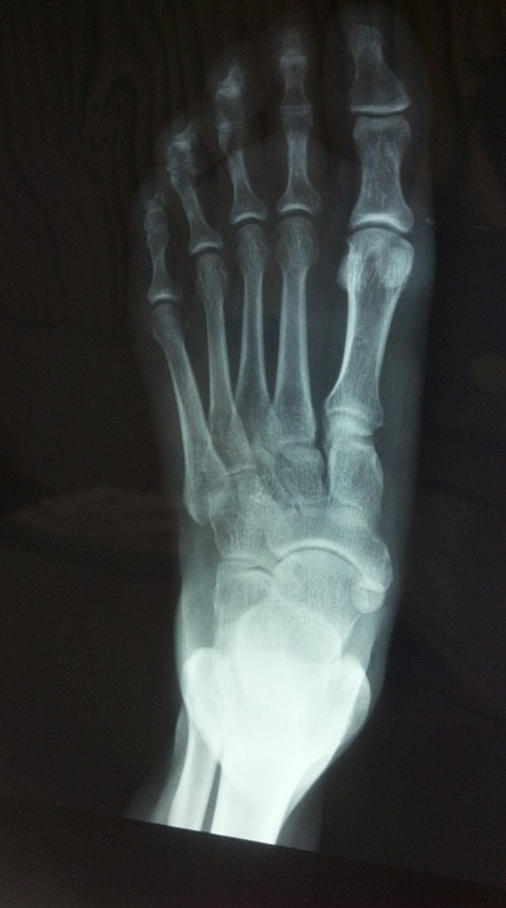

Una de las lesiones más comunes entre los corredores es la denominada fractura por estrés en la parte del antepié o en los metatarsianos. En este caso, la fractura no se considera un traumatismo fuerte con rotura del hueso, sino que se caracteriza por ser una “grieta” en el hueso producida por una serie de repetidos micro-traumatismos o excesiva carga en la estructura ósea.

Este tipo de lesión se suele producir en diferentes zonas del pie. Una de las zonas más comunes es en el segundo metatarsiano, en el dedo con una mayor longitud y, a su vez, con una mayor carga.

Dependiendo del tipo de deporte que el usuario realice, la fractura se encontrará en una zona u otra. En deportes como el baloncesto o el fútbol, se suele localizar este tipo de fracturas en el quinto metatarsiano, ya que los movimientos son más laterales. En cambio, en el caso de los corredores, la zona más común es el calcáneo, ya que en el movimiento deportivo, el primer punto de apoyo del pie es el talón. Sin embargo, existe la posibilidad también de haber una fractura en el astrágalo, es menos común, pero tiene una gran importancia ya que este es el hueso que proporciona el movimiento al pie.